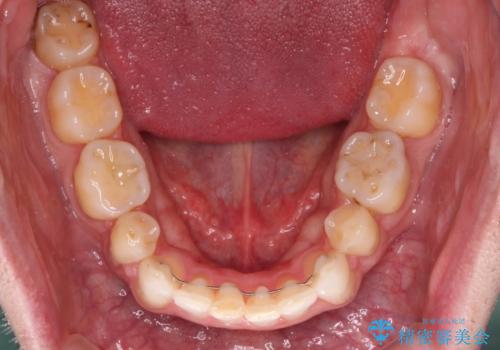

- 上下前歯の叢生を気にして来院された患者様です。

抜歯矯正をした後戻りということで、歯列不正はそれほど大きくなかったため、インビザライン・ライトを用いて矯正治療を行うこととしました。

前歯のデコボコが残っており、シミュレーション通りに動いていない部分がありましたが、再矯正であることやご本人の満足いくところまでデコボコが改善されたとのことで、治療を終了することとしました。